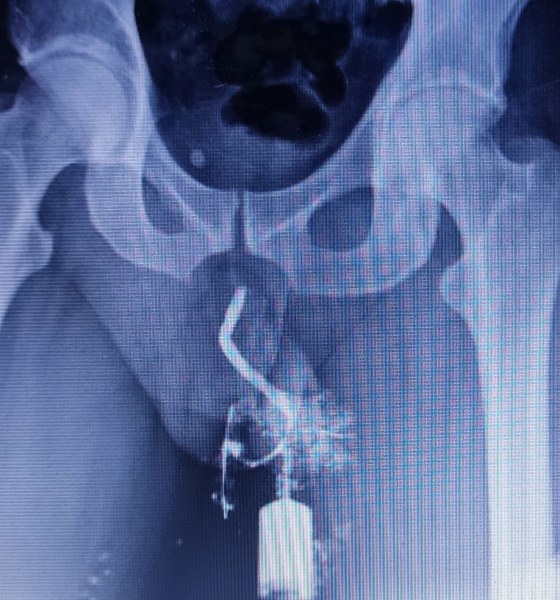

AHI SE APRECIA CLARAMENTE LOS METADATOS ESA FOTO FUE TOMADA EL 26 DE MARZO 4 DIAS DESPUES DE LA MUTILACION GENITAL. SE APRECIA CLARAMENTE COMO TOMARON PIEL DE MI ESCROTO Y LA SUBIERON HASTA ARRIBA. LOS DELITOS QUE SE CONFIGURAN ES MUTILACION GENITAL AGRAVADA, DELINCUENCIA ORGANIZADA "GREMIO DE UROLOGIA DE MERIDA Y TABASCO" Y VARIOS DE CDMX TODOS VAN A SER "D"

SUTURA QUE CERRÓ MI MEATO

AHI SE APRECIA CLARAMENTE LA SUTURA CON LA QUE CERRARON MI MEATO. PARA ESTO NO EXISTE JUSTIFICACION ALGUNA NO PUEDEN INVENTAR NINGUN CUENTO CHINO. TODOS LOS MEDICOS SE PROTEGEN ENTRE ELLOS SI USTED ES VICTIMA DE UNA NEGLIGENCIA MEDICA O DE UN DELITO COMO EL CASO DE SU SERVIDOR TODOS LOS MEDICOS LE VAN A DECIR QUE ESTO ES ALGO NORMAL